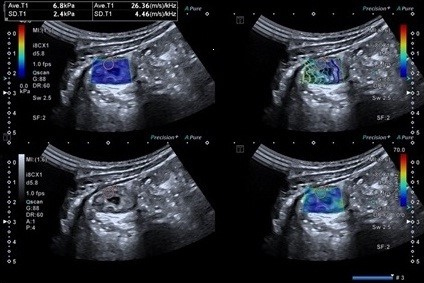

Figure 2. SW image of patient with Short segment ileal narrowing with SWE of 47.8 kPa and SWD of 14.0 m/s/kHz of a patient with terminal ileal kochs.

Group I patients with increased bowel wall thickening >3 mm usually shows some luminal narrowing and on SWE have increased wall stiffness more than 22 kPa with stricture formation. Patients with intestinal Koch usually show wall stiffness of more than 30 kPa (Figure 2). Due to the systematic use of the two-step scheme of evaluation using IUS and SWE, one can not only diagnose inflammatory bowel disease but can also differentiate inflammatory from fibrotic bowel thickening and suggest its etiology [6]. Solarz et al. [7] also in their systematic review suggested the role of SWE as a promising tool to evaluate bowel inflammatory conditions.